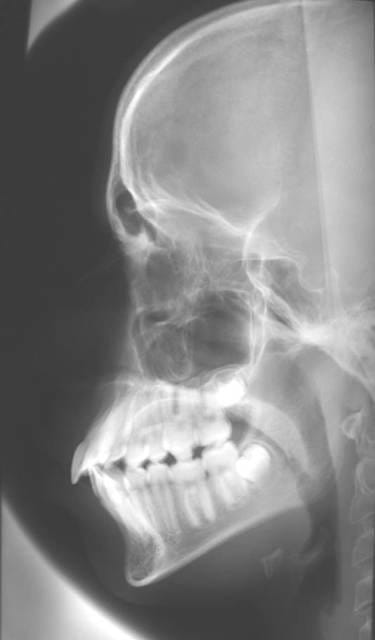

N’étant pas du tout un « pro » de l’interprétation des mesures céphalométriques, pourriez-vous m’indiquer TOUT ce que me cachent ces quatre images :

- d’une part, ce qui est positif [« + »] dans ce bilan 2001 2004, et

- d’autre part, ce qui est négatif [« - »] dans ce même bilan.

Ensuite, me commenter largement ces caractères « + » et « » serait un luxe que j’apprécierai grandement, ainsi que les tendances futures que vous considèreriez comme indispensables pour la suite du traitement.

Ceci dit, on voit un déplacement de l'incisive Sup; associé a la lèvre Sup.

Mais on voit aussi à 13 ans une proximité de la tète du condyle avec le conduit auditif qui, s'il ne s'agit pas d'un erreur de tracé doit donner de grandes, d'énormes, douleurs condyliennes.

Voici une copie de la télé 2004 : pas évident de distinguer.

Tu es devant une Cl. III. sans doute par un hypodéveloppement du Max. Sup. Comme on n'est pas en grandeur réelle je ne peux faire que des proportions. Celle de 5/6 entre la base du crane Po/Na et Xi/Pm n'est pas respectée.

Ou le Max. est trop petit, ou la Md. est trop grande, ou les deux à la fois.

D'autre part tu es en bout à bout cuspidien. Cl. 0.5. Ce qui est tres défavorable. C'est la pire des occlusions. Avec une version des incisives Sup. éxagérée.

A vu de nez, car il manque enormemant de chose sur ce tracé(desole tu as dis dire ce que l'on pense), je ne trouve pas l'incisive sup trop versée.

les rx ont elles ete prises dans les meme conditions? la premieres en innoclusion et la deuxieme dents serrees?

y a til encore de la croissance? meme s'il a 13 A

Il est vrai qu'a vue de nez, les molaires sont en classe 2 angle en debut de traitement avec un big ANB au debut, qui s'est bien réduit comme le souligne catrose

Une proalveolie sup de suceur de pouce , bien réduite 3 ans aprés.

L'ANB s'est surtout réduit..parce que le patient ferme la bouche sur la deuxieme radio! -donc le point B "avance" et l'angle se réduit). La premiere radio n'est vraiment pas exploitable, l'inocclusion est complète.

La proalvélie sup s'est LEGEREMENT réduite (prendre comme référence l'angle entre l'incisive sup et le plan palatin), tout comme la proalvéolie inf s'est légèrement accentuée (voir par rapport au plan mandibulaire): c'est simplement une compensation dento-alveolaire de la cl.II squelettique, les incisives "cherchant" un contact.

Il n'existe, à priori, pas de signes radiologiques évidents pour affirmer que cette CLASSE II BIPRO (mais oui, Bjc!!!) soit celle d'un suceur de pouce car:

-le décalage antéro-post n'est pas considérablement plus fort au niveau incisif qu'au niveau molaire(faudrait voir une radio initiale en occlusion, ou des moulages...)

- il ne semble pas y avoir de beance initiale ds le sens vertical (idem....)

- généralement, il existe une bascule anti-horaire du plan palatin/Plan de Francfort chez les suceurs de pouce...

Le diagnostic d'une déglutition infantile ne peut reposer que sur une observation clinique, certainement pas sur un cliché radio. De plus les téléradios sont censées etre prises en PIM, et non en position de repos ou durant la déglutition. Une eventuelle déglutition infantile n'empeche pas de prendre un cliché en occlusion: il y a une erreur du manipulateur radio durant le premier cliché, c'est tout...(tu noteras qu'il n'est pas pris en Francfort horizontal non plus ce premier cliché, deuxième erreur...)

Ok, le point A semble avoir légèrement reculé (les tracés sont-ils fiables?), mais je mesure un ANB de 5,5, valeur d'une cl.II légère, qui correspond d'ailleurs à une cl.II dentaire assez discrète également (apparemment 1/2 cuspide).